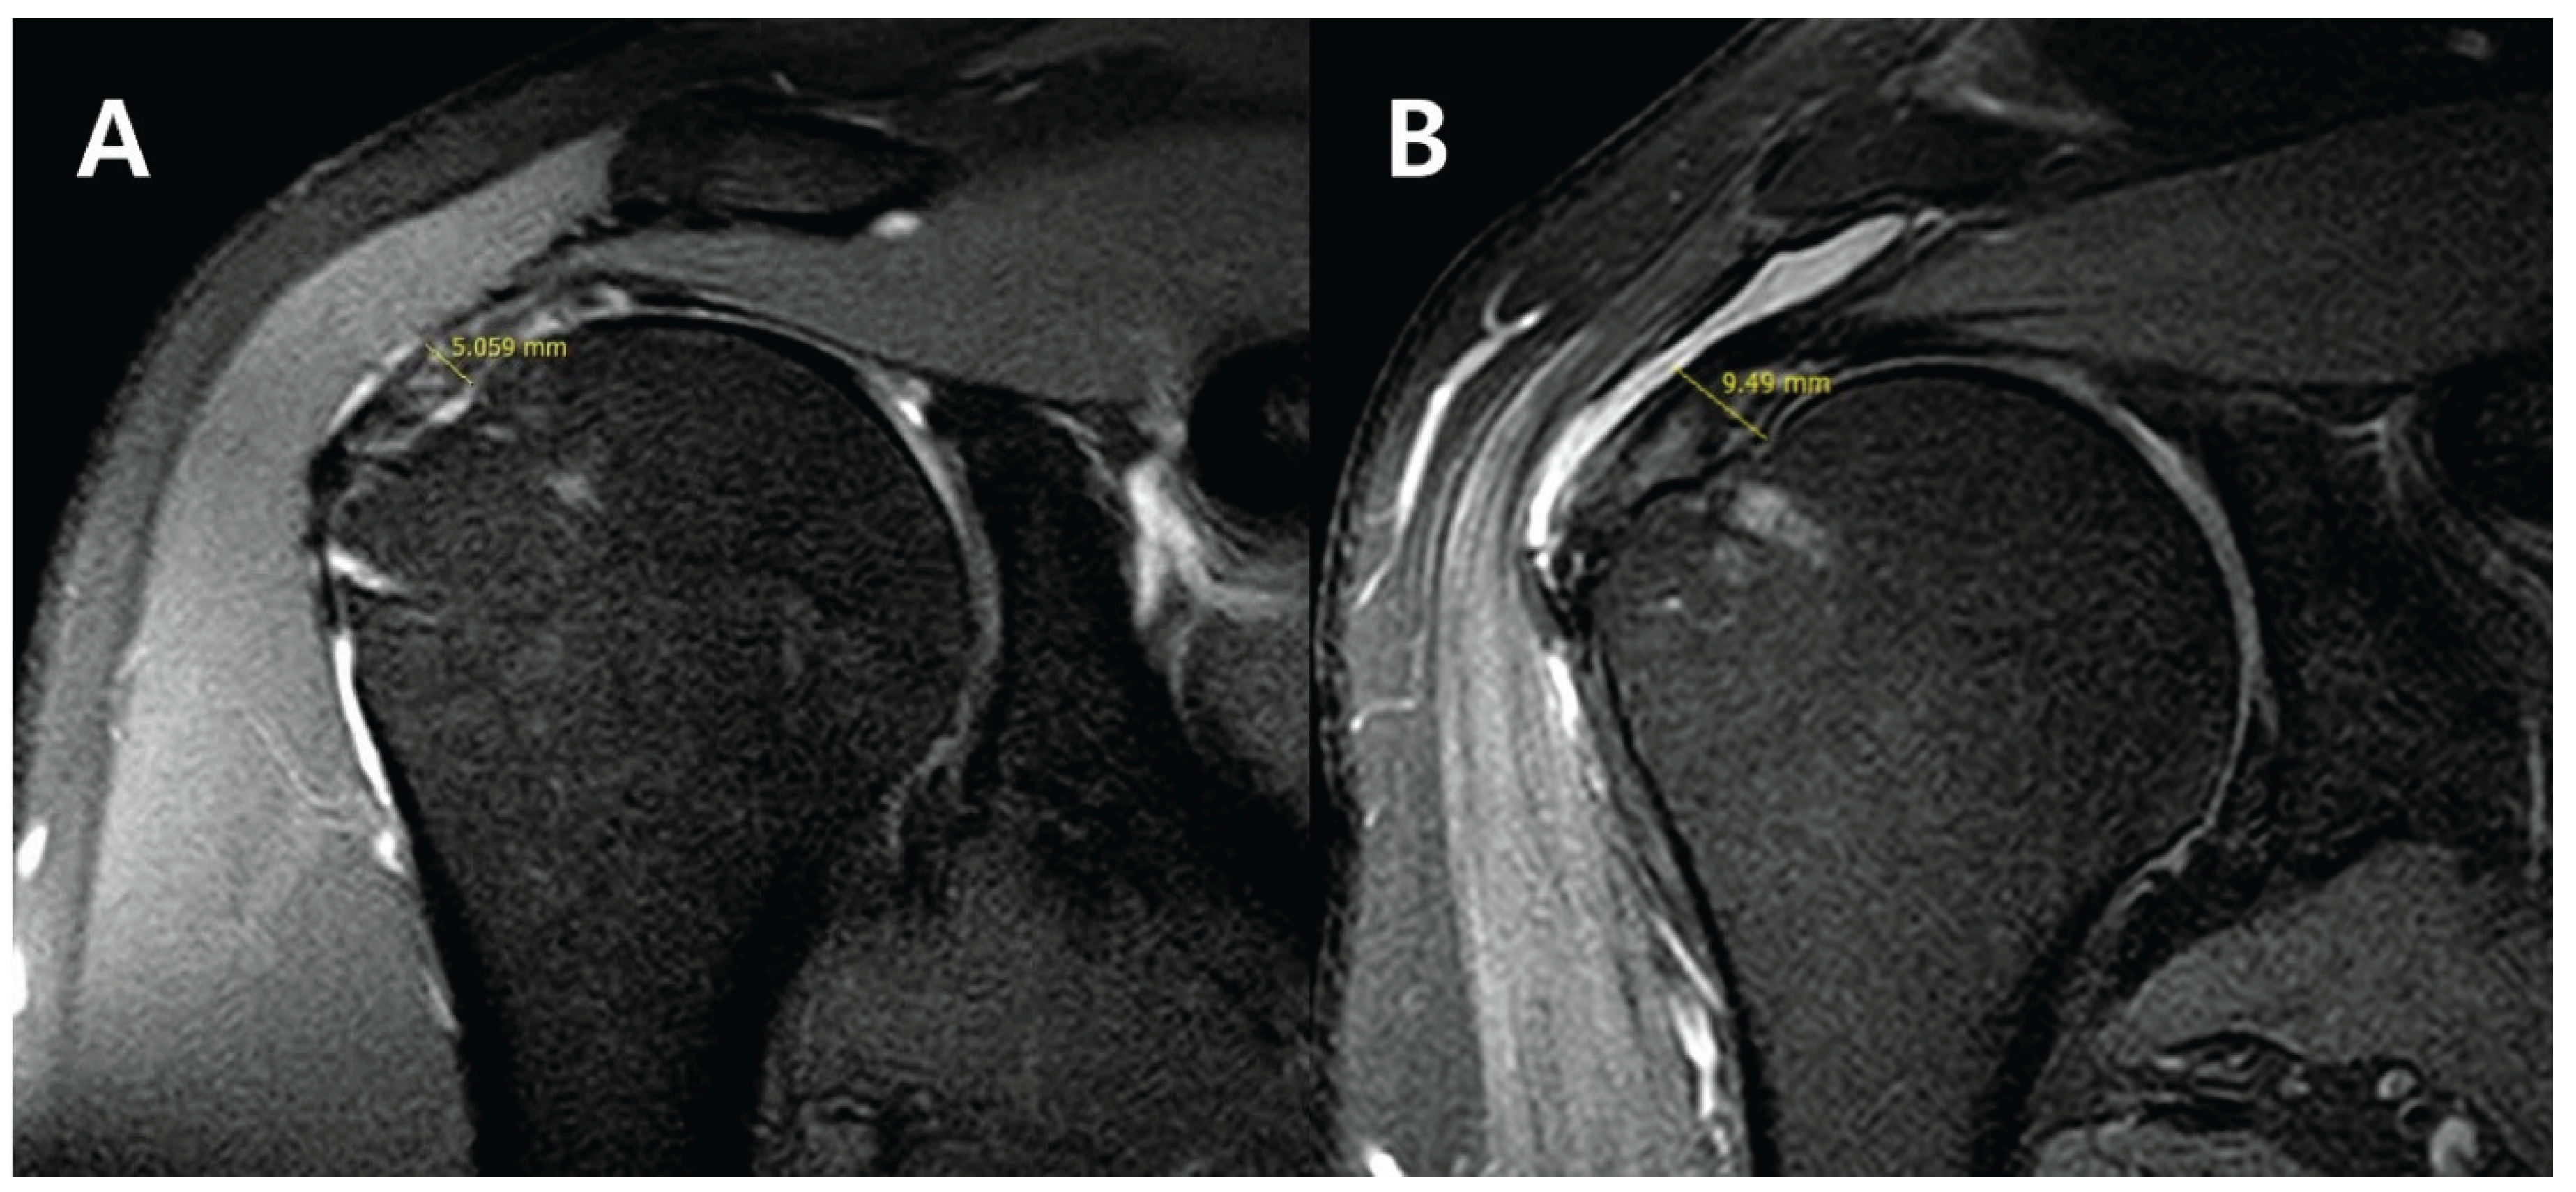

Background Sugaya type III rotator cuff re-tears are defined by a supraspinatus tendon thickness reduced to 50% or less of normal. These patients often experience prolonged pain and functional impairment. When considering reoperation, the burden of a long-term rehabilitation process and high risk of re-tear poses significant challenges for both patients and surgeons. Bioinductive collagen implants possess a mechanism that promotes the formation of new tendon tissue, holding potential to accelerate recovery and reduce re-tears. However, studies applying this technique in patients with Sugaya type III re-tear have not yet been reported. This study aimed to evaluate the clinical and radiologic outcomes of applying this procedure in patients with Sugaya type III re-tear. Method: This retrospective case series (Level IV) study included 15 patients (mean age 61.7 years) with Sugaya type III re-tears confirmed by MRI. All patients underwent arthroscopic rotator cuff repair combined with biologically induced collagen implant augmentation. Clinical outcomes were assessed at preoperative, 6-month, and 12-month postoperative time points using VAS, ASES, SANE, and WORC scores. Imaging findings were assessed via MRI, measuring supraspinatus thickness, and evaluating joint range of motion (ROM) and implant failure. Thickness measurements were performed twice each by an orthopedic surgeon (15 years' experience) and a radiologist (9 years' experience), with mean values used and intra- and inter-observer reliability (ICC) calculated. Results: The average VAS score decreased significantly from 6.5 ± 1.0 to 2.1 ± 0.8 (p < 0.001), and the ASES score improved from 45.2 ± 8.5 to 78.5 ± 8.9 (p < 0.001). SANE and WORC scores also showed significant improvement from 41.0 ± 12.1 to 81.4 ± 9.8 and from 39.6 ± 10.7 to 83.3 ± 10.1 respectively (p < 0.001). Supraspinatus thickness on MRI recovered from 4.5 ± 2.2 mm to 6.9 ± 2.5 mm (p < 0.001). At the final follow-up, all patients’ recovery of full or near-full range of motion was observed, and no implant failure were observed at either 6-month or 12-month follow-ups (0%). For MRI measurements, the inter-observer ICC was 0.93 (95% CI 0.85–0.97), and the intra-observer ICC ranged from 0.94 to 0.95. This indicates a high level of reliability. Conclusion: This study represents the first application of arthroscopic reattachment combined with bioengineered collagen implant augmentation in patients with Sugaya type III rotator cuff re-tears. Short-term follow-up confirmed significant improvement in pain and function, restoration of tendon thickness, and a 0% graft failure rate. This procedure is considered a useful method for treating patients with Sugaya type III re-tear, minimizing rehabilitation periods and avoiding the risk of re-tear.